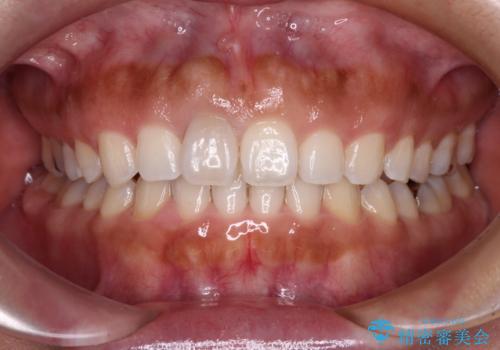

- 上の前歯の出っ歯と閉じにくい口元を気にして来院された患者様です。

口元を積極的に引っ込めるために、上顎左右の小臼歯1本ずつ抜歯することとしました。

ワイヤー装置にて矯正治療を行っていましたが、急な転勤で毎月の通院が難しくなってしまいました。

抜歯したスペースは概ね閉じていたので、インビザラインに切り替えて通院回数を減らし、治療を継続していくこととしました。

突出していた口元がスッキリと仕上がり、患者様には大変満足していただきました。